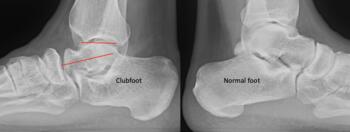

As the Ponseti grew in popularity, I noted significant discrediting of surgical options. Well long-term studies on the Ponsetti are starting to surface, and it is not without its own problems. Kids are lost to follow-up, not braced appropriately, and just like we saw in long-term studies with the posteromedial release, there is a lot of undercorrection. Casting cannot and will not ever achieve what the Cincinnati release can. Although the Ponseti may not have the complications of the Cincinnati, X-ray data reveals that the Ponseti cannot and does not correct everything, most critically, talocalcaneal angles. You can not solve a clubfoot with an Achilles tenotomy and an overly aggressive casting. As these kids develop, I see residual met adductus and calcaneal varus, along with casting complications like flat top talus and met primus elevatus. I then see that they will develop DJD just like posteriomedial and Cincinnati releases. Haasbeck and team in 1997 reported that the Cincinnatti required fewer procedures than the posteromedial release over the life of their study.14 Thomas performed a systematic review in 2019, concluding that the longer the study follow-up, the greater the relapse rate and the poorer the results of the Ponseti.15 For most of us who have done clubfeet surgery for many years, this is no surprise. Among the 46 studies meeting inclusion criteria, they saw as high as 67 percent required future surgeries to address relapse.15

So, to summarize, true congenital clubfeet have abnormal talar bodies, which lead to abnormal ankle and subtalar joints with short Achilles and tight posterior tibial tendons. Regardless of treatment, there is nothing anyone can do to make the talus a normal bone. Many of these cases can and will develop additional deformities. Only the Cincinnati release can address every issue associated with the deformity, but it is NOT a cure. The Ponseti procedure is a total compromise, also NOT a cure. The sooner everyone treats the Ponseti as a compromise, I believe we will be far happier with the outcomes. I remember discussing this with others treating pediatric orthopedic issues during the rise of the Ponseti in the early 2000s. We all agreed, undercorrecting the deformity will lead to more surgeries and residual deformities. Until we all face the reality that clubfeet are a genetic deformity and not just a positional deformity, we will never make them perfect. Thus, athletes and the military will put any and all clubfeet patients to the test. There is no doubt that exceptions exist, but in time, at least based on our limited review of over 1000 clubfeet and 250 cases we saw in the military, no one is immune to complications, arthritis, and ultimately disability.

Here is a typical case presentation. A 21-year-old Marine at Ft. Leonard Wood for training underwent a Cincinnati release at one year old and had stellar follow-up. Her surgeon even wrote her medical waiver for entrance into the Marines. She ran track in high school. She finished boot camp and completed all of her Marine training, but now has chronic pain. She no longer can run. She hasn’t passed her physical training in over a year. She developed talonavicular DJD. By all accounts, her overall clubfoot should be rated an A+; no residual deformity, normal talocalcaneal angles on AP and lateral views, no equinus, no residual varus, only slight met primus elevatus, but no signs of a flattop talus. Clinically, she lacks subtalar range of motion, which I commonly find post-clubfoot release of any kind. So many in the military do very well for a while, but the demands of the military eventually catch up to them. We all root for clubfeet to make it, but the odds are stacked against them.